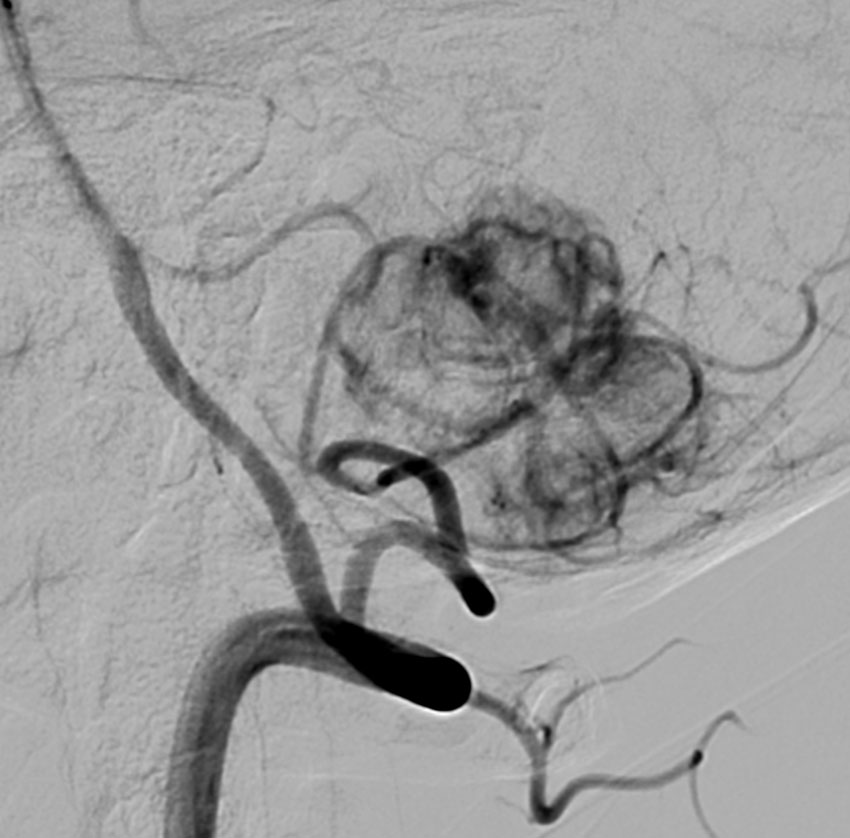

- 椎骨動脈撮影では,著明な腫瘍濃染像(血管がいっぱい)がみられて確定診断が可能です

左小脳にできた小さな のう胞性血管芽腫です。矢印の先にある小さな塊だけが腫瘍で周囲は腫瘍から染み出した液体が溜まっています(のう胞といいます)。右側は血管撮影とMRIを組み合わせた画像で,腫瘍に動脈が流入しているのが見えます。

右のPICAが主たるfeeding arteryです。でもPICAのretromedullary segmentからshort feedersが流入していますから,油断をすると延髄背側障害という厳しい手術合併症を生じる可能性は十分あります。この腫瘍は正中後頭下開頭で全摘出できましたし,神経脱落症状を残していません。難易度は中等度のものです。